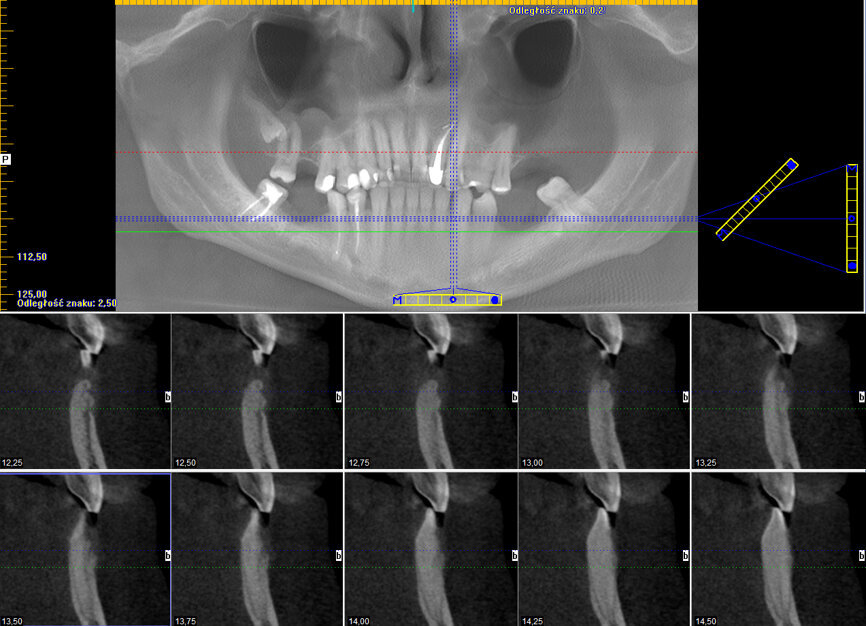

Wykonano CBCT szczęki i żuchwy (Ryc. 1), w którym stwierdzono zmiany okołowierzchołkowe przy zębach 27, 28 i 47, stan po leczeniu kanałowym zębów 22 i 45, zatrzymany ząb 18 w położeniu mezjalno-kątowym, pogrubienie błony śluzowej w zachyłku zębodołowym zatoki szczękowej lewej, w badaniu widoczny był również ubytek osteolityczny kości z destrukcją przedsionkowej blaszki kostnej, owalnego kształtu o wymiarach 7 x 4mm, zlokalizowany pomiędzy zębami 32 i 33.

Ryc. 1: CBCT wykonane przed leczeniem.